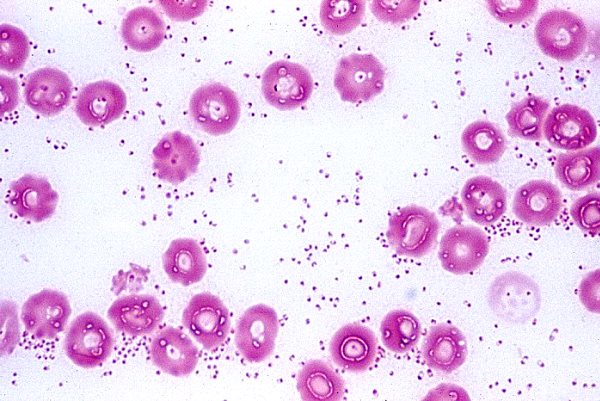

Bệnh vi khuẩn này được coi là phổ biến ở nhiều loài động vật, bao gồm cả con người. Sau này thường bị nhiễm Pasteurella từ vật nuôi. Tác nhân gây bệnh cho lợn là vi khuẩn bất động Pasteurella multocida týp A và D và Pasteurella haemolytica. Các dấu hiệu của bệnh tụ huyết trùng rất khác nhau tùy thuộc vào loài động vật mà vi khuẩn được nuôi cấy.

Pasteurella có 4 nhóm huyết thanh được phân loại: A, B, D, E. Tất cả các nhóm này đều giống nhau về ngoại hình và đặc tính kháng nguyên. Pasteurella trông giống như những que hình bầu dục bất động dài 1,5-0,25 micromet. Đề cập đến vi khuẩn gram âm. Không tạo thành tranh chấp. Tất cả các giống Pasteurella đều phát triển trên cùng một môi trường dinh dưỡng, thích sự hiện diện của máu trong nước dùng.

Bức ảnh chụp một lá phổi của một con lợn bị chết do tụ huyết trùng.

Sau khi nhận được vật liệu sinh học trong phòng thí nghiệm, việc phân lập pasteurella và xét nghiệm sinh học trên chuột cũng được thực hiện.